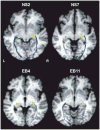

Multiple functional methods including functional magnetic resonance imaging, transcranial magnetic stimulation, and positron emission tomography have shown cortical reorganization in response to blindness. We investigated microanatomical correlates of this reorganization using diffusion tensor imaging and diffusion tensor tractography (DTT). Five early blind (EB) were compared with 7 normally sighted (NS) persons. DTT showed marked geniculocalcarine tract differences between EB and NS participants. All EB participants showed evidence of atrophy of the geniculocortical tracts. Connections between visual cortex and the orbital frontal and temporal cortices were relatively preserved in the EB group. Importantly, no additional tracts were found in any EB participant. Significant alterations of average diffusivity and relative anisotropy were found in the white matter (WM) of the occipital lobe in the EB group. These observations suggest that blindness leads to a reorganization of cerebral WM and plausibly support the hypothesis that visual cortex functionality in blindness is primarily mediated by corticocortical as opposed to thalamocortical connections.